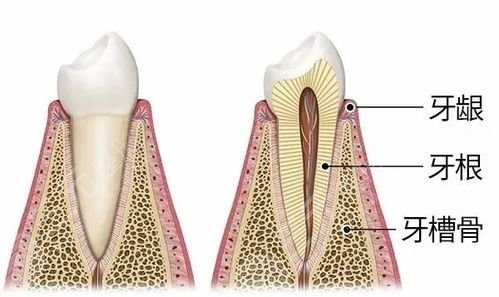

雅博士牙齿种植案例

雅博士口腔医院牙齿种植案例

患者下排牙齿缺失长期,主要佩戴假牙,不适感明X,采用Allon4种植,使用四颗种植体,就能保Z下排牙齿正常的支撑力量。种植后外观美学和功能兼具,咬合功能良好,需要一段时间适应新种植牙齿。